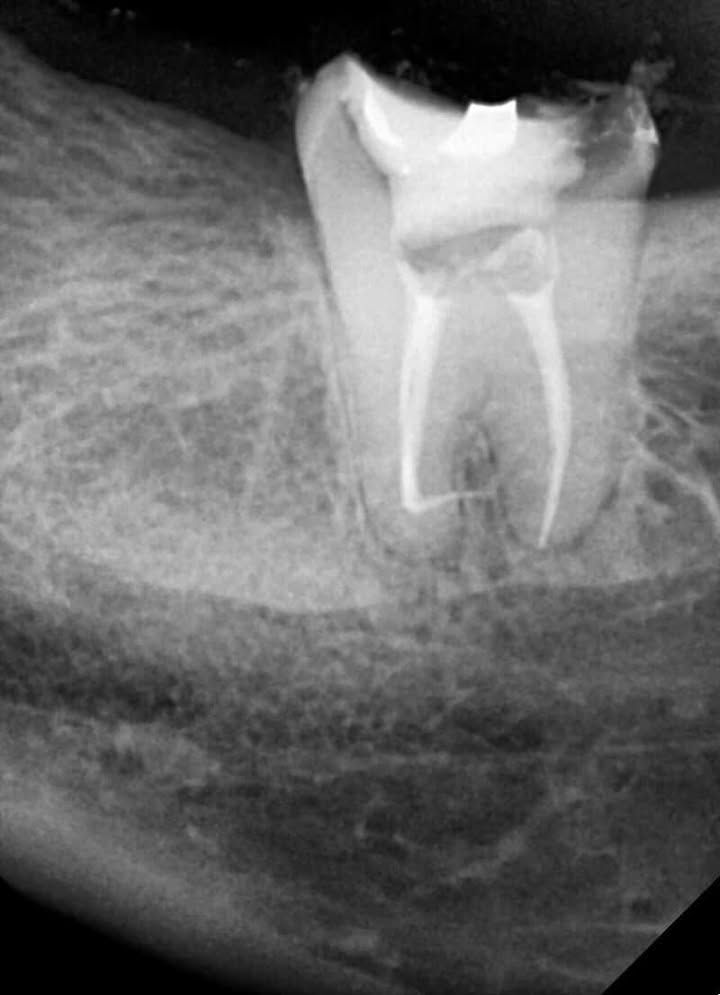

Final shaping of the canals was safely completed using EZ Shaper Pro (EZ2) files. Due to the extreme curvatures, enlargement was kept conservative. - Obturation

Final obturation was performed using the single cone technique with bioceramic sealer.

This advanced endodontic case demonstrates the importance of proper technique, patience, and the right instrumentation when treating teeth with symptomatic irreversible pulpitis and complex root canal anatomy. The combination of careful scouting, pre-curved files, conservative shaping with EZ Shaper Pro, and single-cone obturation with bioceramic sealer led to a successful outcome.